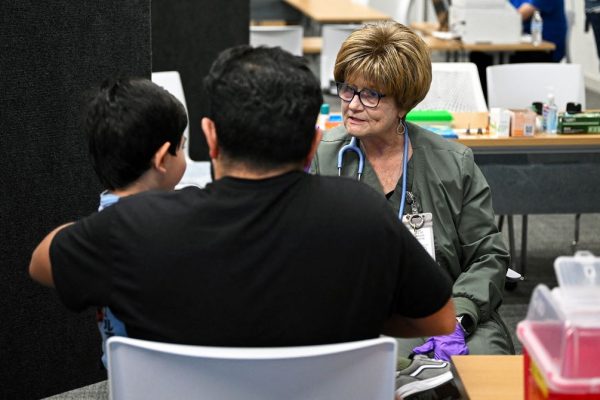

The US is experiencing its worst year for measles in over three decades, with more than 1,300 cases in 40 states as of July 16. Cases were almost as high in 2019, putting the country’s measles elimination status at risk. Six years ago, health officials were able to stop the spread. But amid growing public…